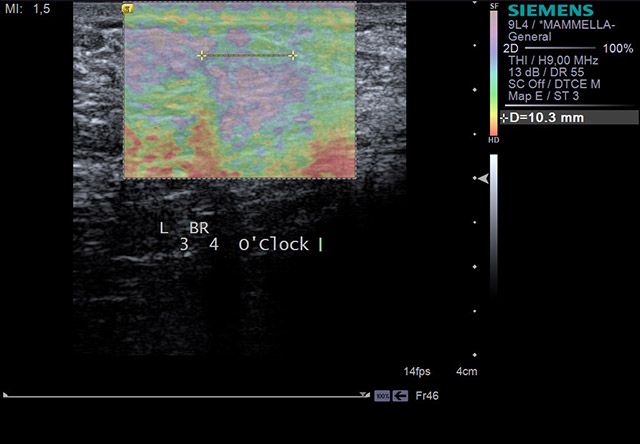

Η ελαστογραφία μαστού είναι μια νέα και πολλά υποσχόμενη απεικονιστική μέθοδος που επιτρέπει στους επιστήμονες να διαγνώσουν τα καλοήθη ογκίδια, ξεχωρίζοντας τα από τους κακοήθεις όγκους αλλά και τις ύποπτες για κακοήθεια αλλοιώσεις στο μαστό.

Είναι ουσιαστικά μια νέα τεχνική στους υπέρηχους, που ασκεί μια μικρή πίεση στους εντοπισμένους όγκους, μετρώντας την ελαστικότητά τους. Ο καρκίνος γενικά εμφανίζει μεγαλύτερη σκληρότητα, επομένως η ελαστογραφία μπορεί να δώσει τις αναγκαίες πληροφορίες έτσι ώστε να μειώσει τις βιοψίες μαστών μόνο στις απόλυτα απαραίτητες.

Γίνεται δυνατή η υποκατάσταση της βιοψίας με βελόνα, ιδιαίτερα στα όργανα στα οποία η προσπέλαση με βελόνα είναι τραυματική και δύσκολη. Η υπερηχογραφία και η ελαστογραφία φθάνουν κοντά στην ιστολογική διάγνωση όχι μόνο στα επιφανειακά όργανα (θυρεοειδής, λεμφαδένες, μαστός), αλλά και στα εν τω βάθη όργανα (ήπαρ, πάγκρεας, νεφρός, προστάτης, μήτρα, ωοθήκες).